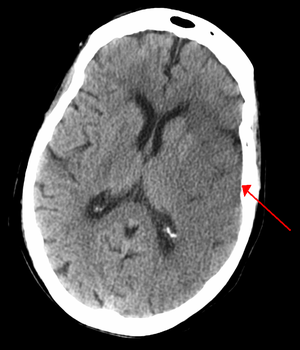

CT scan slice of the brain showing a right-hemispheric ischemic stroke (الجانب الأيسر من الصورة). | |